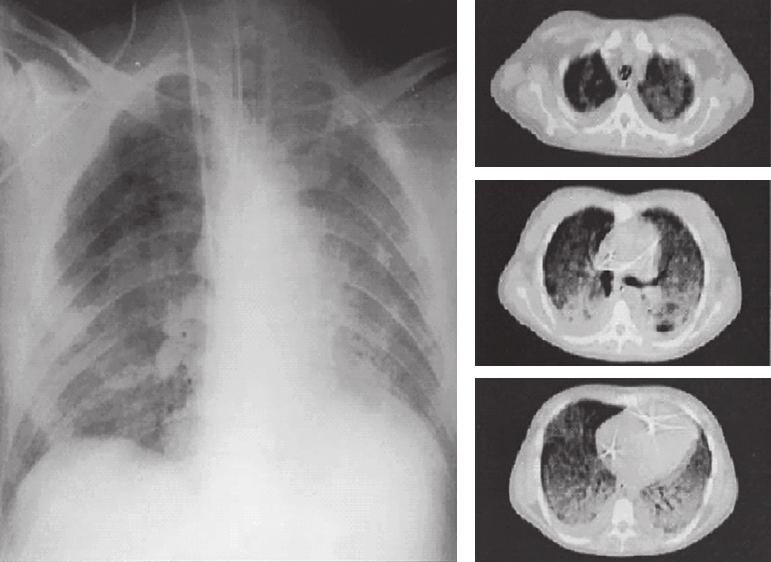

一般认为,ARDS具有以下临床特征:①急性起病,在直接或间接肺损伤后72h内发病,一般不超过7d;②常规吸氧后低氧血症难以纠正;③肺部体征无特异性,急性期双肺可闻及湿啰音,或呼吸音减低;④早期病变以间质性为主,胸部X线片常无明显改变。病情进展后,可出现肺内实变,表现为双肺野普遍密度增高,透亮度减低,肺纹理增多、增粗,可见散在斑片状密度增高阴影,即弥漫性肺浸润影(图6-2);⑤呼吸功能不全无法完全用心力衰竭或液体超负荷解释。柏林新定义已给出明确的ARDS诊断标准。

图6-2 急性呼吸窘迫胸部X线、CT表现